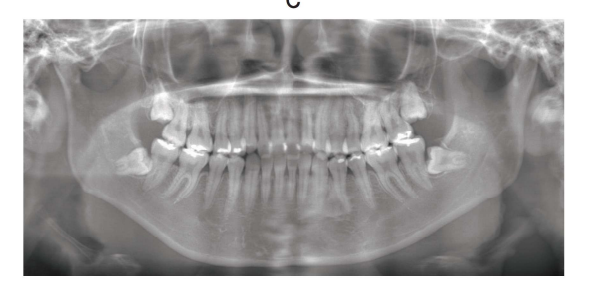

118回 A-77

22 歳の女性。上顎の歯並びが悪いことを主訴として来院した。診断の結果、抜歯を伴うマルチブラケット装置を用いた矯正歯科治療を行うこととした。初診時の顔面写真(別冊No. 25A)、口腔内写真(別冊No. 25B)及びエックス線画像(別冊No. 25C)を別に示す。セファロ分析の結果を図に示す。

解答:b

解説:

セファロ:下顎骨小さめ、上顎中切歯唇側傾斜

叢生:上顎 目立つ、下顎 スペースなさそうだが叢生ではない

臼歯関係:両側Ⅱ級

叢生具合から上顎のみの抜歯でよさそう。4番か5番で悩む。

5番を抜歯すると、前歯部の叢生を改善するのに時間がかかり、奥歯も移動するので更にⅡ級がひどくなると予想。なので4番を抜歯。